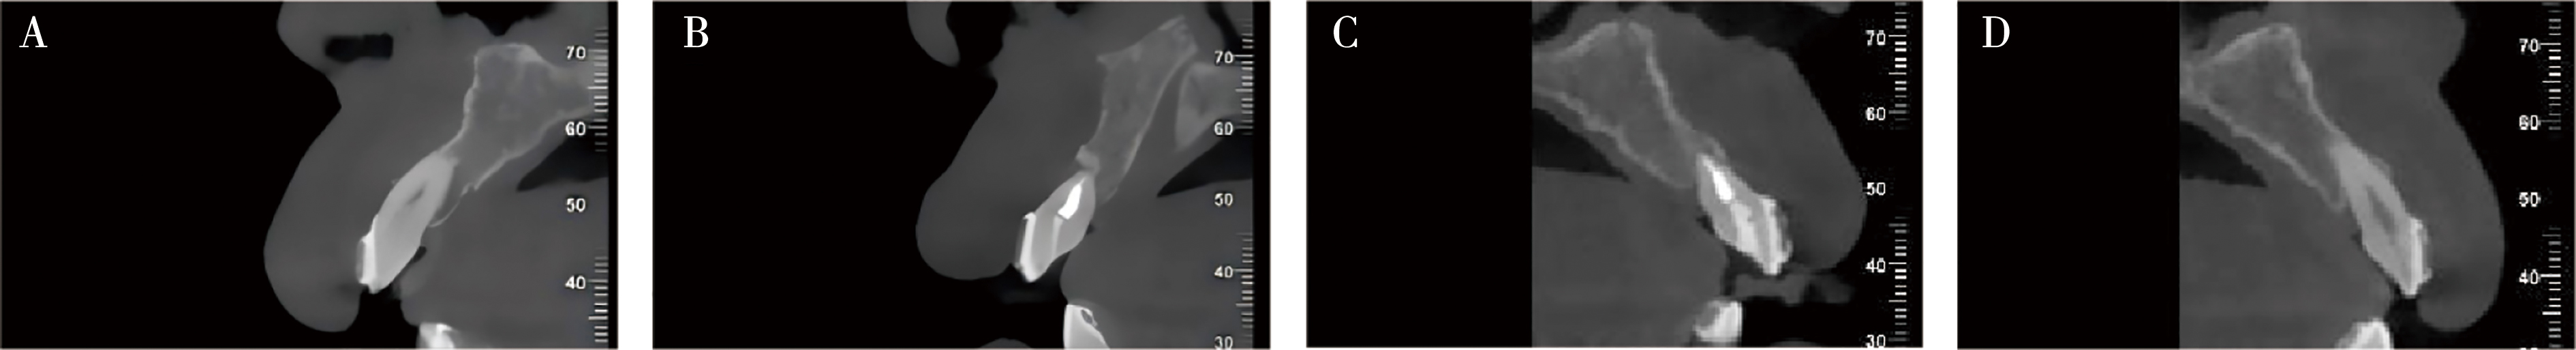

Zhang CR, Liu Q, Yang JW, et al. A digital technique for splinting periodontally compromised mobile teeth in the mandibular anterior region[J]. J Prosthet Dent, 2021, 125(4): 560-563.

Liu YC, Bai SZ, Zhong S, et al. Digital workflow for periodontal splinting with a guided device[J]. J Esthet Restor Dent, 2023, 35(4): 621-624.